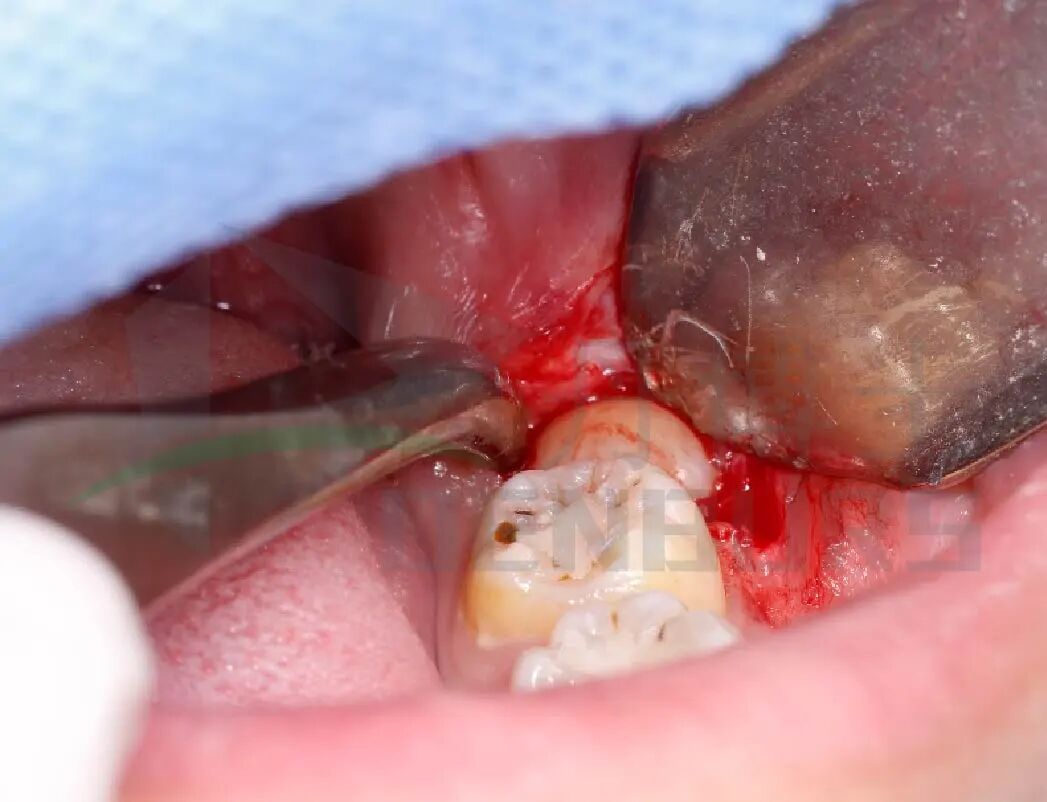

3)逐次拔除

此处邻牙阻力尚未解除,选择用C33L.317.016车针,沿牙冠中线,从远中向近中磨除,分冠为颊侧/舌侧两块,再分块拔除。